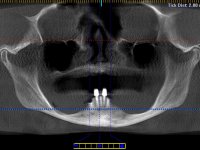

Two dental implants were planned in the CBCT scan, in the area of the inferior canines. The dental extractions were performed and, simultaneously, the alveolar crest was flattened and the implants were placed. Three issues were considered while implant placement: parallelism of the axis, same height of the implant’s neck, and same position in the coronal plan. This 3D insertion is essential to have a good retention of the overdenture in the future. Patient’s removable denture was fixed in the dental lab, to include the extracted teeth, and a soft-tissue relining was done over the healing abutments. After the osseo-integration period, a first impression was done with an open-tray and a doble-mix technique. This dental impression allowed the production of screwed wax-rims and an individual tray for a functional impression. A second impression, final, was done with an individual tray with a monophasic silicone. The occlusal wax-rims were correct in the mouth according to the full denture guidelines. Special care was taken with the occlusal vertical dimension and the support in the soft-tissues. A silicone bite registration material was used to better defined the intermaxillary relations. Teeth set-up was done in the dental lab with the selected tooth color. Due to the fact that the base was screwed to the dental implants, the teeth set-up was functionally evaluated in the mouth. Another silicone bite registration material was used to allow final occlusal adjustments. Finally, the locators were screwed and the retention nylons were selected according to the patient needs.